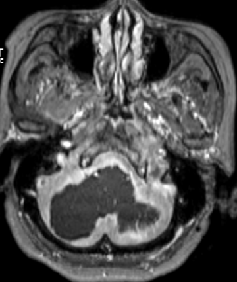

2013-5-16 MRI